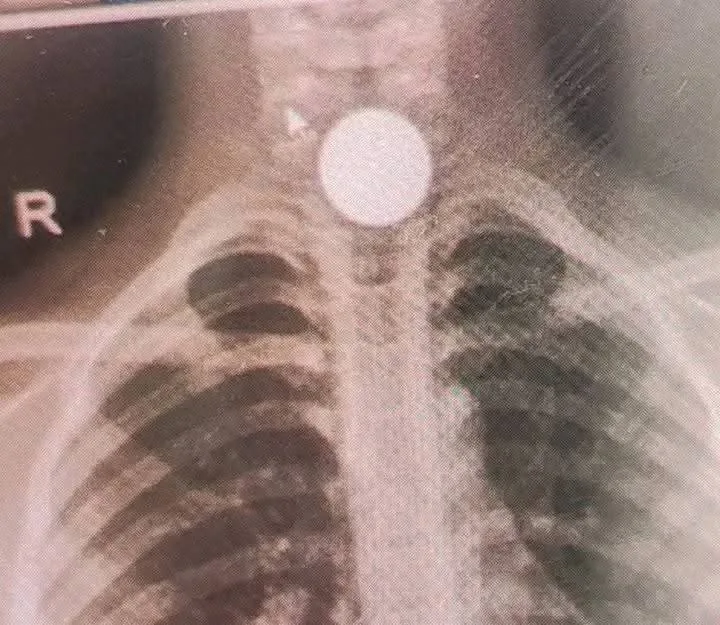

La difusión de una imagen radiográfica del pequeño generó gran alarma entre los usuarios. Sin embargo, la incertidumbre dio paso al alivio cuando el Hospital Roosevelt emitió un comunicado aclarando la situación. Confirmaron que el niño recibió la atención inmediata y especializada por parte de su equipo pediátrico, incluyendo la cirugía necesaria, la cual resultó exitosa. Lo más alentador es que el menor fue dado de alta dos días atrás y ahora se recupera en su hogar. El hospital también desmintió los reportes de solicitudes de ayuda económica, asegurando que brindaron todos los recursos necesarios para la recuperación del pequeño.

Ante la preocupación generada en redes sociales por el caso de un niño de 5 años que ingirió una moneda en Uspantán, Quiché, el Hospital Roosevelt salió al paso para aclarar la situación. Si bien el incidente ocurrió el pasado 30 de abril y requirió el traslado del menor a la capital para una cirugía, el centro médico aseguró que la intervención se realizó con éxito y el paciente ya se encuentra en casa con una evolución favorable. Asimismo, desmintieron categóricamente cualquier solicitud de fondos que pudiera estar circulando en nombre del hospital, enfatizando que el niño recibió toda la atención necesaria de forma gratuita. Las autoridades hicieron un llamado a la población a verificar la información a través de sus canales oficiales.